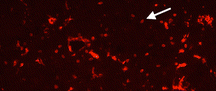

Microglia

UCR School of Medicine Professor of Biomedical Sciences Byron Ford’s laboratory studies the neuroprotective roles of neuregulin-1 (NRG-1) and other compounds in stroke and other acute neuroinflammatory disorders. Researchers utilize in vivo and in vitro models as well as high-throughput tools to scan the genome, transcriptome, proteome and metabolome to understand mechanisms associated with neuronal pathology and neuroinflammation following acute brain injuries. NRG-1 is currently in human clinical trials and showed significant efficacy in a phase II study of heart failure patients. The results of these studies have therapeutic implications for other acute neuroinflammatory disorders include traumatic brain injury, nerve agent toxicity, cerebral malaria and sepsis.